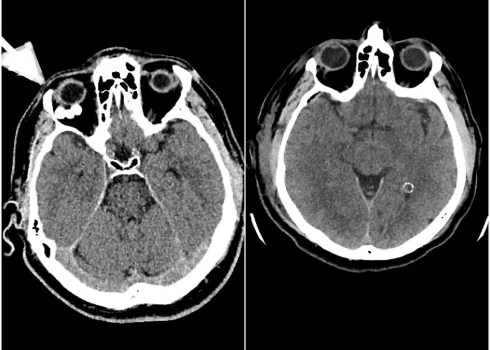

Ļoti retos gadījumos veic datortomogrāfiju. Tādos gadījumos parasti diagnosticē iekšējās trūces.